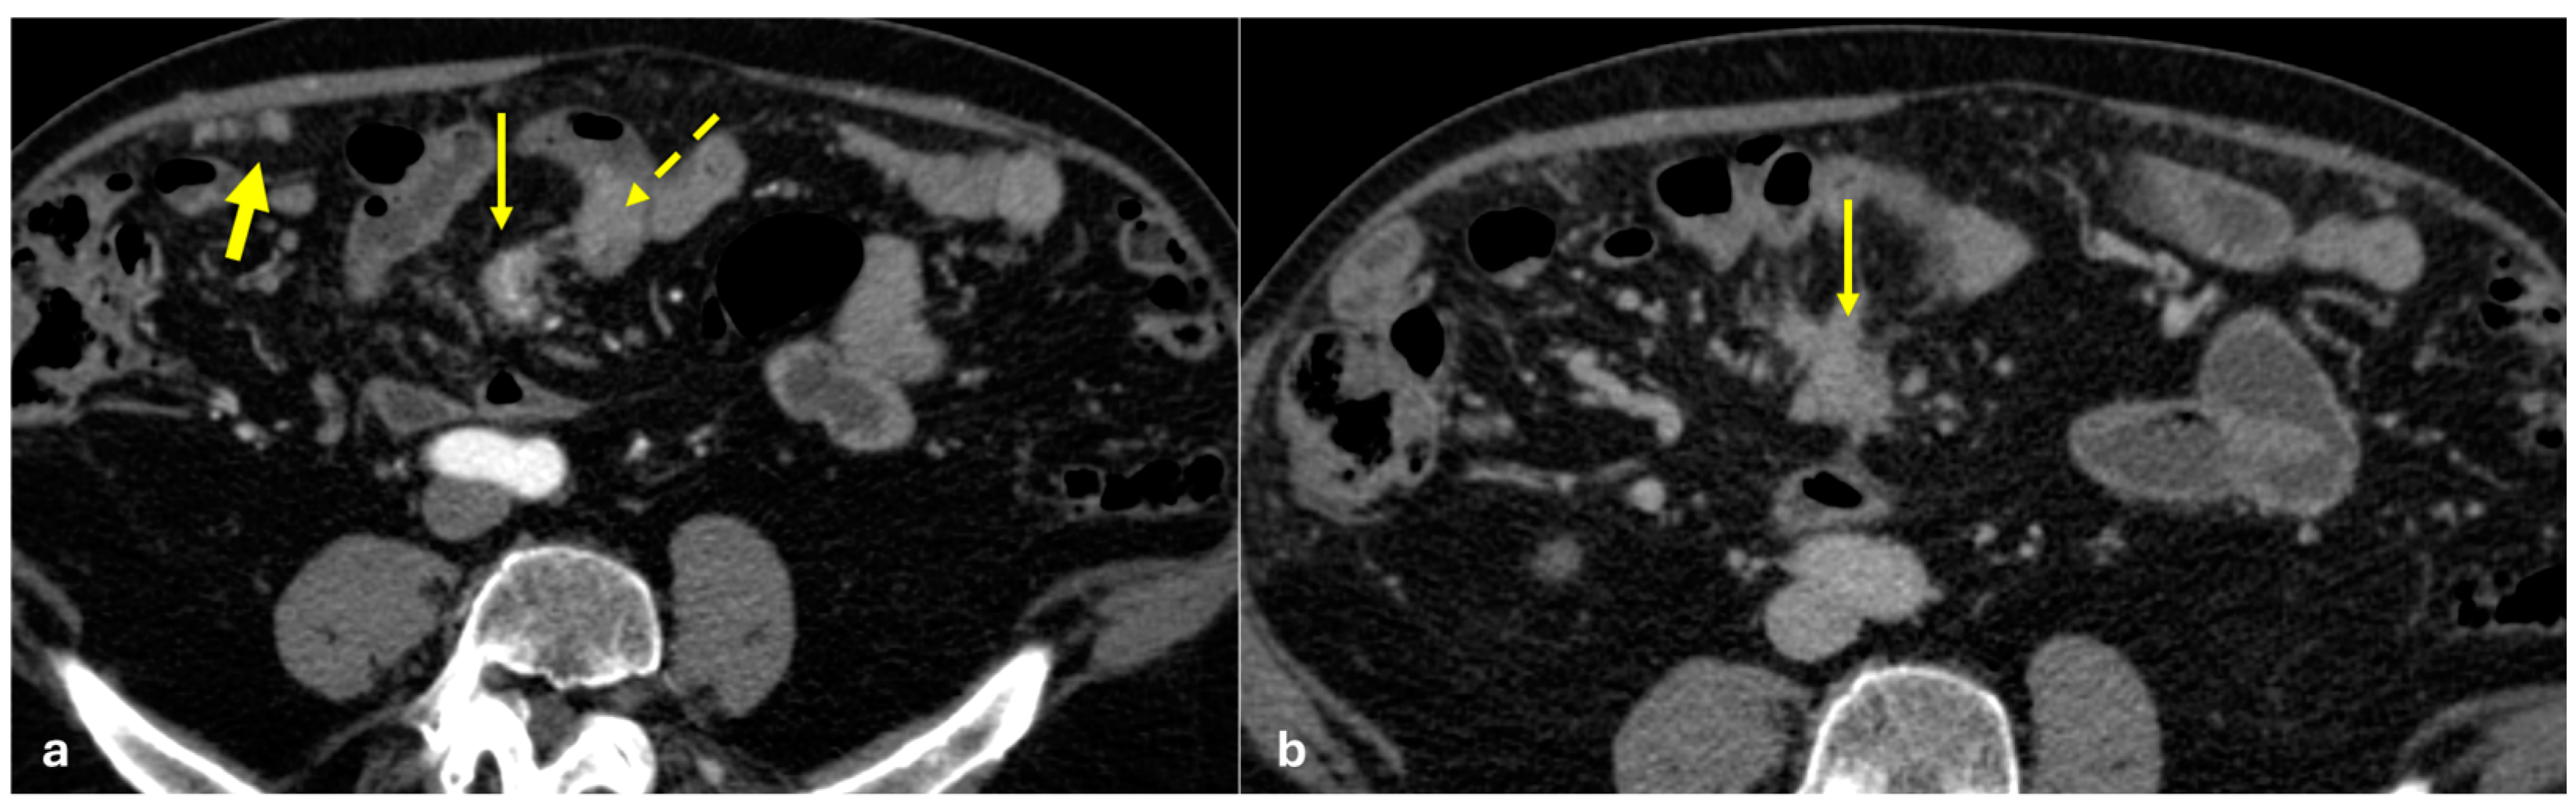

- Micro-nodular pattern: micro-nodules with a diameter ≤ 5 mm (Figure 1);

- Nodular pattern: nodules with a diameter > 5 mm (Figure 2a);

- “Omental cake”: nodular thickening of the omentum (Figure 2b);

- Plaque pattern: confluent nodular plaques, typically involving the lower surface of the right diaphragm (Figure 3);